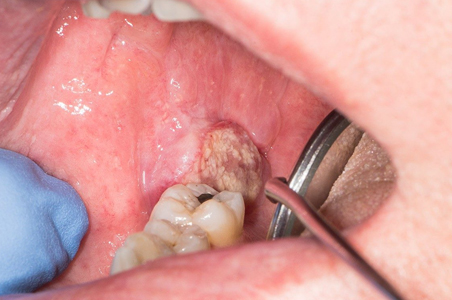

Oncology is the branch of medicine focused on the prevention, diagnosis, and treatment of cancer. It encompasses a wide range of specialties including medical oncology, radiation oncology, and surgical oncology. Medical oncologists treat cancer with medications like chemotherapy, immunotherapy, and targeted therapy. Radiation oncologists use radiation therapy, while surgical oncologists perform surgery to remove tumors

• Surgical Oncology